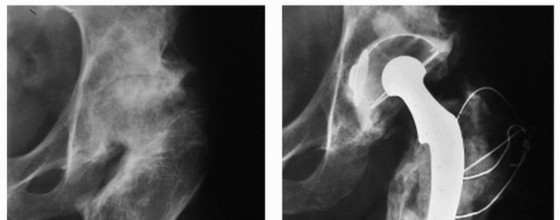

Head-Sparing Procedures for Osteonecrosis of the Femoral Head INDICATIONS/CONTRAINDICATIONS Osteonecrosis of …